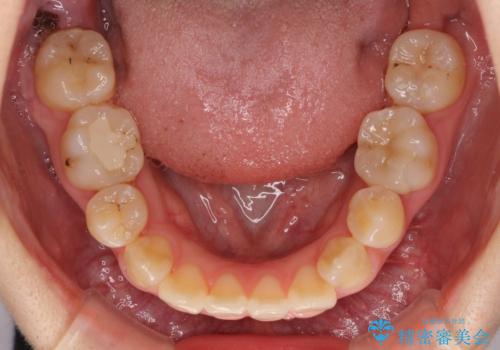

- 奥歯が痛いとのことで来院された患者様です。

上顎親知らず周辺の炎症と、神経組織の失活した歯の炎症による痛みが認められたため、親知らずの抜歯と根管治療を行いました。

根管治療を行った歯はクラウンによる補綴治療が必要となりますが、高校生の頃に行った矯正治療の後戻りも気になるとのことで、補綴治療を行う前に矯正治療を行うこととしました。

後戻りは軽度であり、インビザラインにて歯列を整え、その後にオールセラミッククラウンにて補綴治療を行うこととしました。